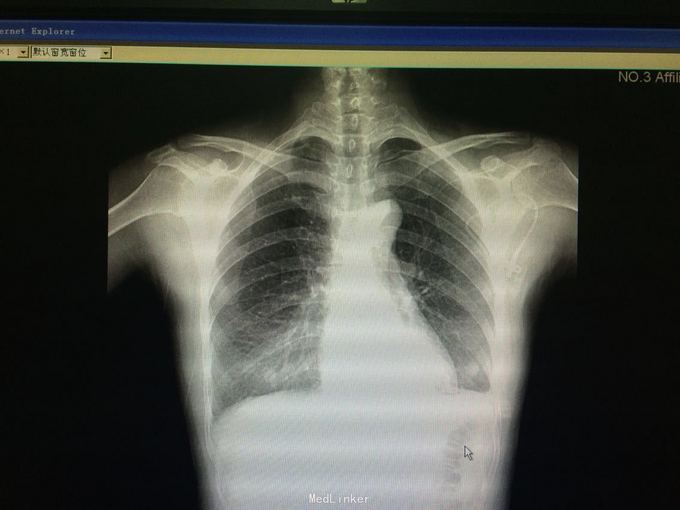

诊断:左侧气胸,高血压1级、中危。 入院后予胸腔穿刺加闭式引流排气术,并予头孢咗肟预防感染治疗。负压引流瓶未及气泡冒出、听诊左肺呼吸音明显增强后予夹管复查胸片,示左肺气胸较前好转。